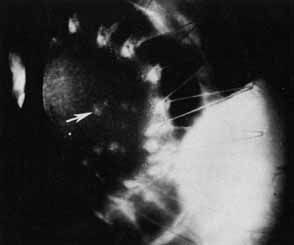

One of the techniques used for posterior chamber intraocular lens implantation during penetrating keratoplasty is iris fixation.19 A 6-mm, three-piece modified J-loop, 0-degree or 10-degree angulated Prolene haptic, four-hole intraocular lens can be used. It is suture-fixated to the posterior aspect of the iris with 9-0 Prolene on a blunt-tapered needle (Fig. 9). The lens is held securely in place with the haptics positioned within or posterior to the ciliary sulcus. As opposed to the old style of iris-fixated intraocular lenses, pseudophacodonesis is nearly nonexistent, and torsion of the intraocular lens along the fixational point axis does not seem to occur, probably because of the stability provided by the haptics posterior to the iris.

Fig. 9 Visual results of suture-fixated posterior chamber lenses during penetrating keratoplasty. Using a BVIOO-4 Ethicon needle, two prolene sutures are placed through the midperipheral iris, one at approximately 3 o'clock and one at 9 o'clock. Each suture also passes through one hole in the optic of the intraocular lens with the knots being tied between the iris and the anterior surface of the optic. The haptics of the lens are positioned at 3 o'clock and 9 o'clock within the ciliary sulcus. (From Price FW Jr, Whitson WE: Visual results of suture-fixated posterior chamber lenses during penetrating keratotomy. Ophthalmology 96:1234, 1989, with permission)